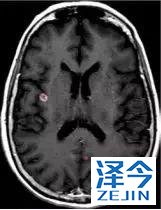

脑转移病变显示缩小了95%!

初始, 2018年6月 3周期 2018年8月